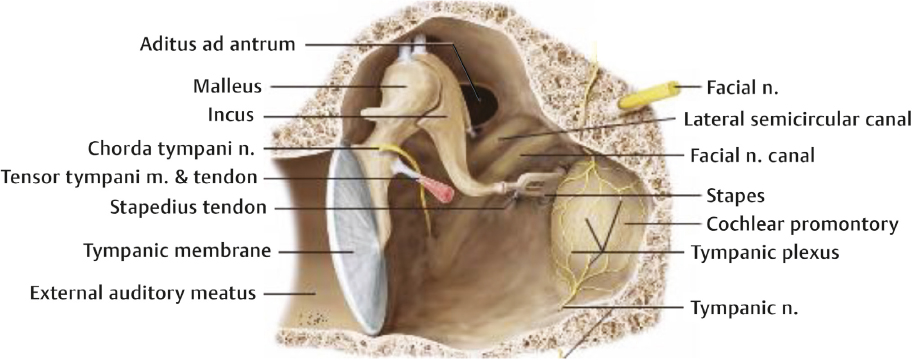

КТ анатомия сосцевидного отростка: особенности и показания